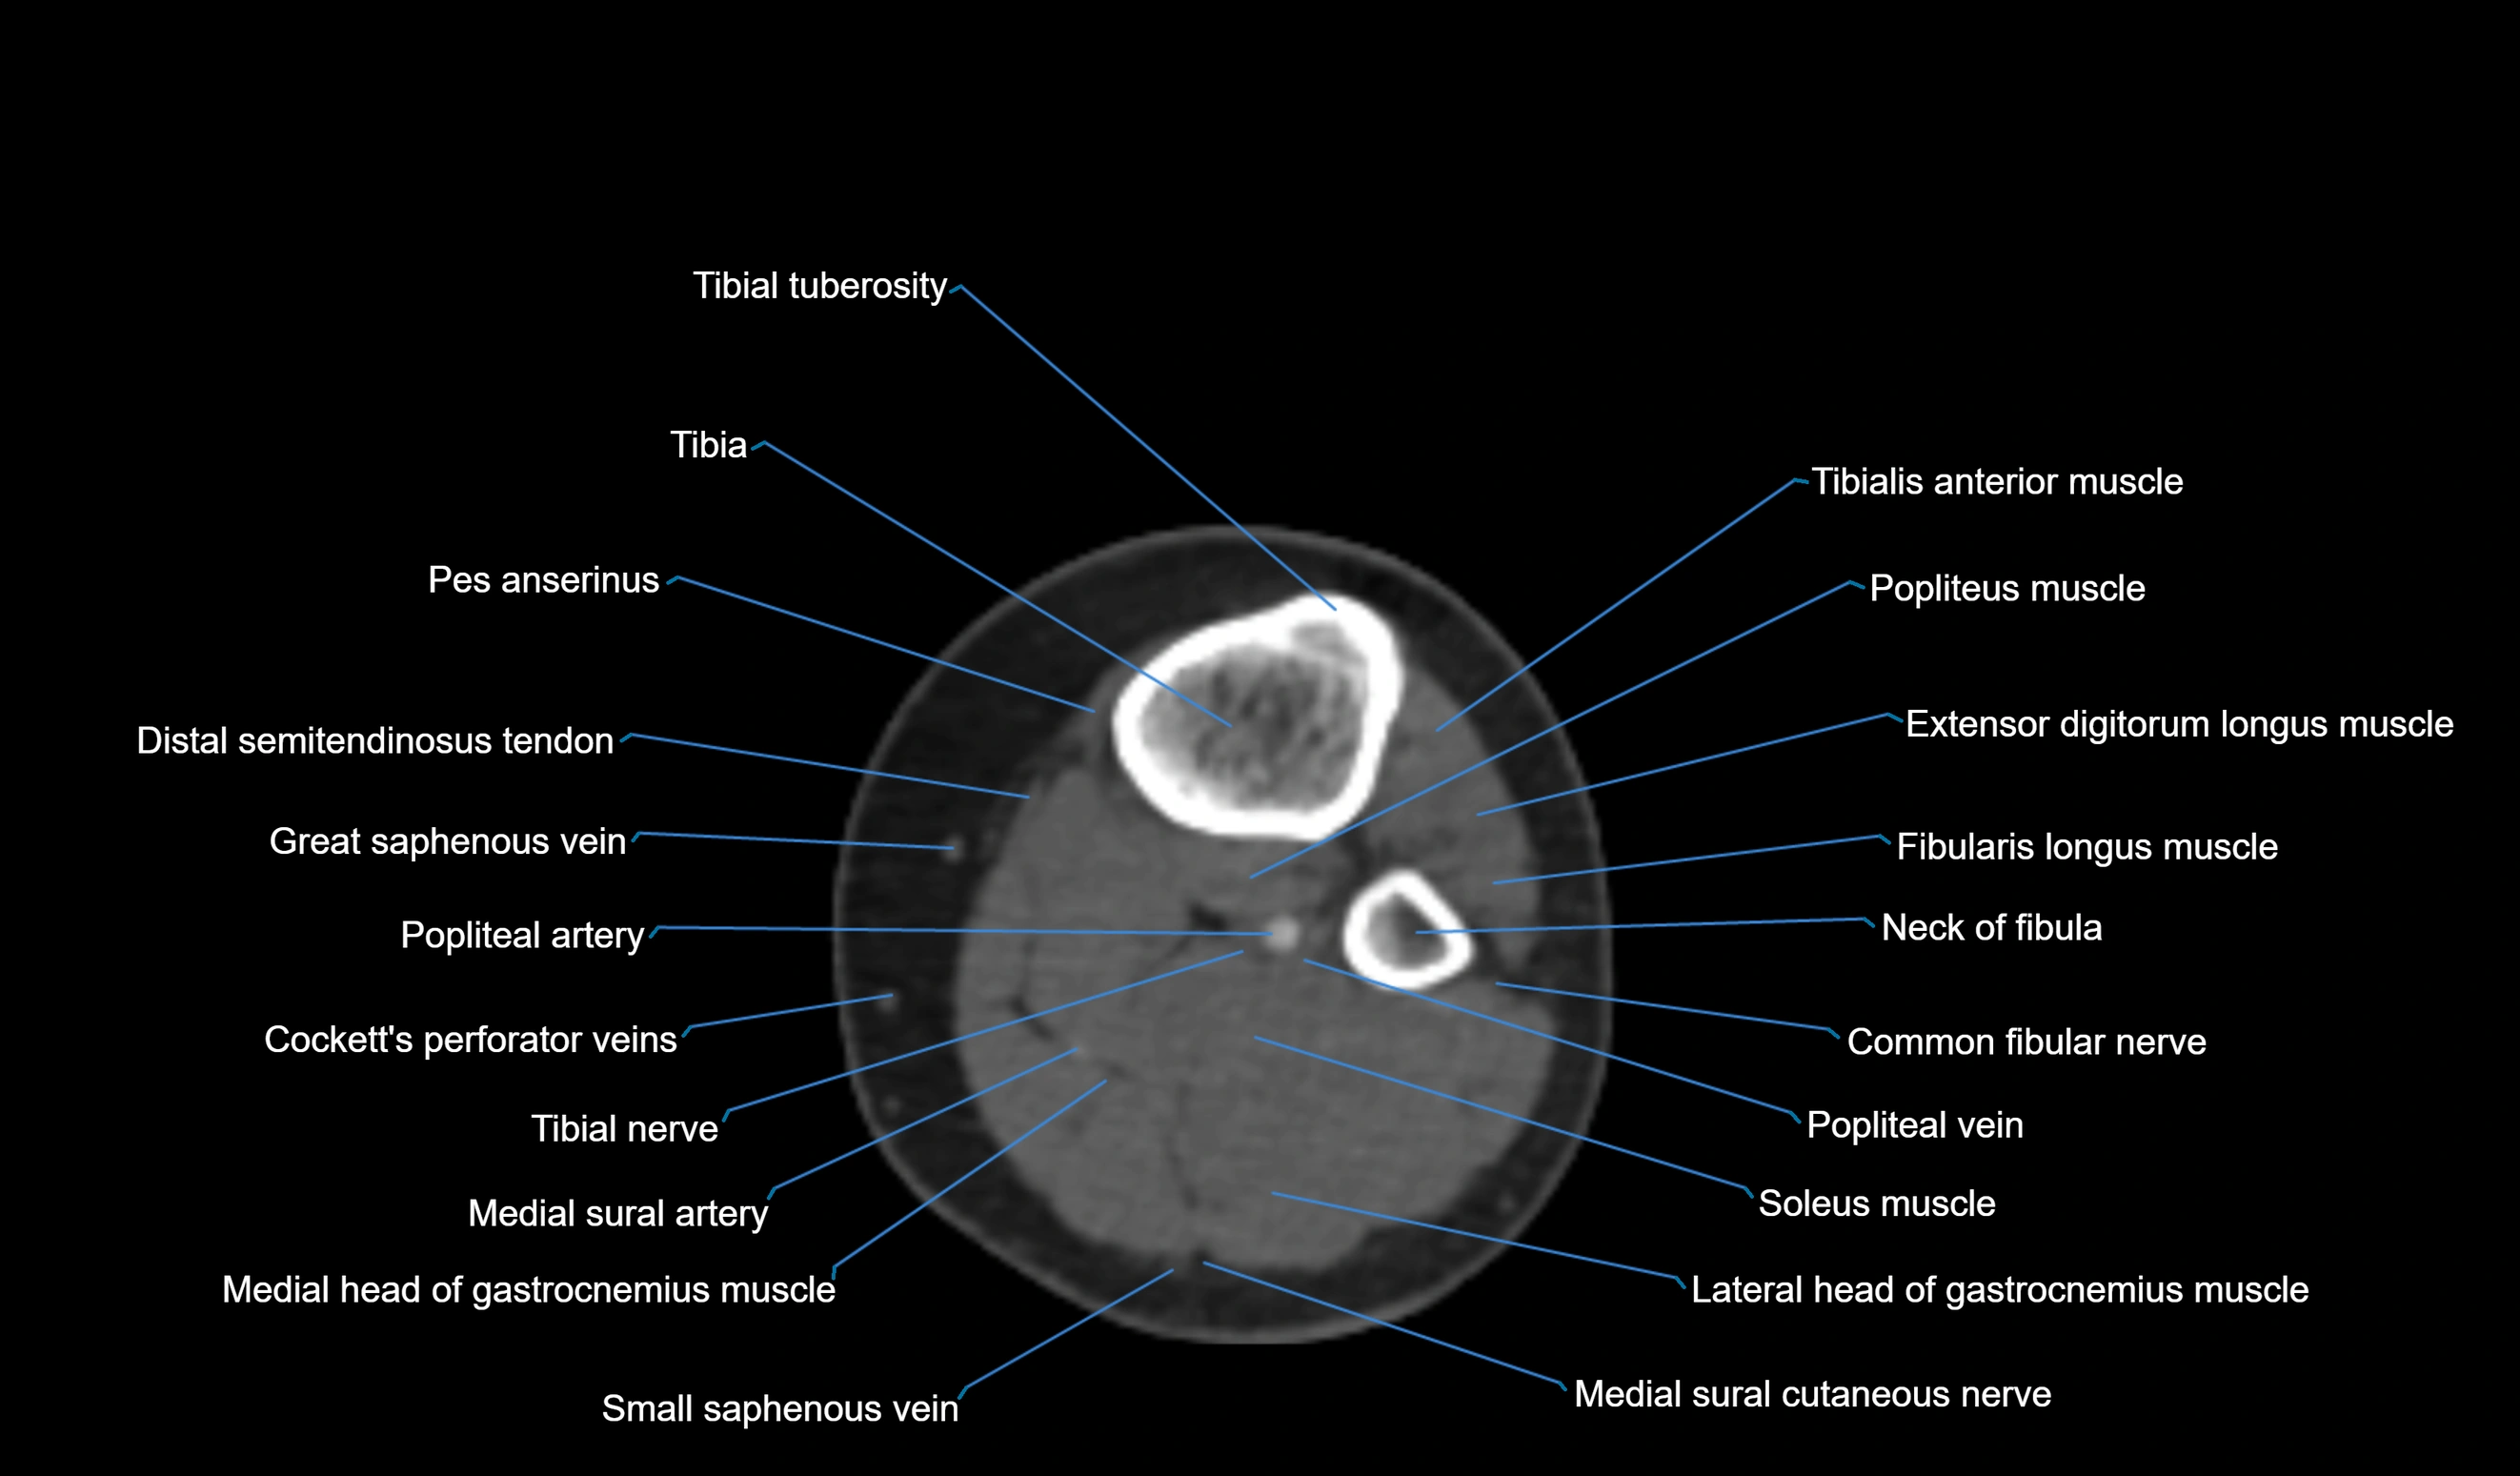

- Tibial tuberosity

- Tibia

- Gerdy’s tubercle

- Popliteus muscle

- Tibialis anterior muscle

- Extensor digitorum longus muscle

- Fibularis longus muscle (peroneus longus muscle)

- Neck of fibula

- Common fibular nerve

- Popliteal vein

- Popliteal artery

- Tibial nerve

- Medial head of gastrocnemius muscle

- Lateral head of gastrocnemius muscle

- Soleus muscle

- Medial sural cutaneous nerve

- Small saphenous vein

- Distal semitendinosus tendon

- great saphenous vein